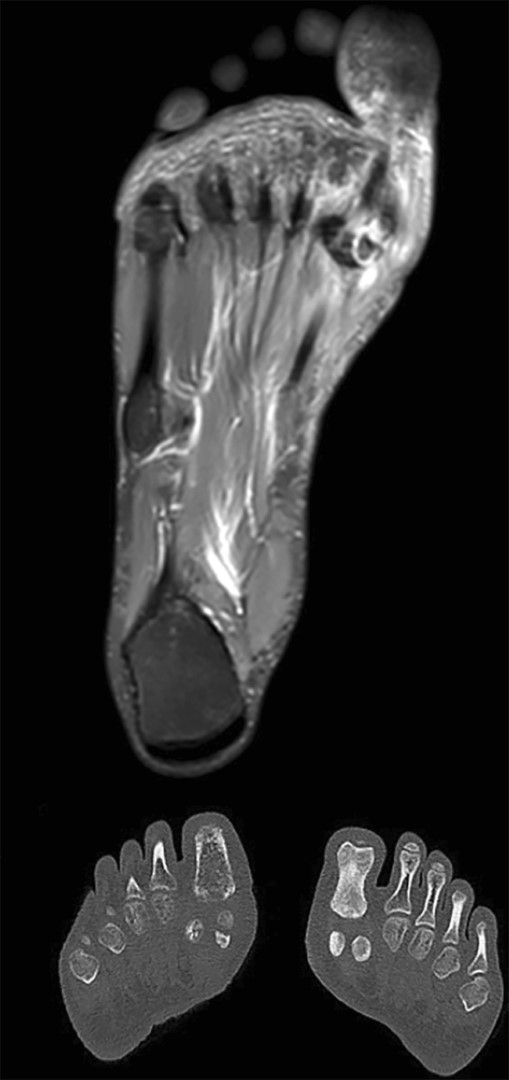

After three weeks, in addition to swelling, the patient exhibited redness and warmth in the right hallux, with a significant increase in pain. An MRI was repeated, which indicated a bipartite medial sesamoid versus fracture of the medial sesamoid, with signs of joint effusion (Figure 1).

Figure 1